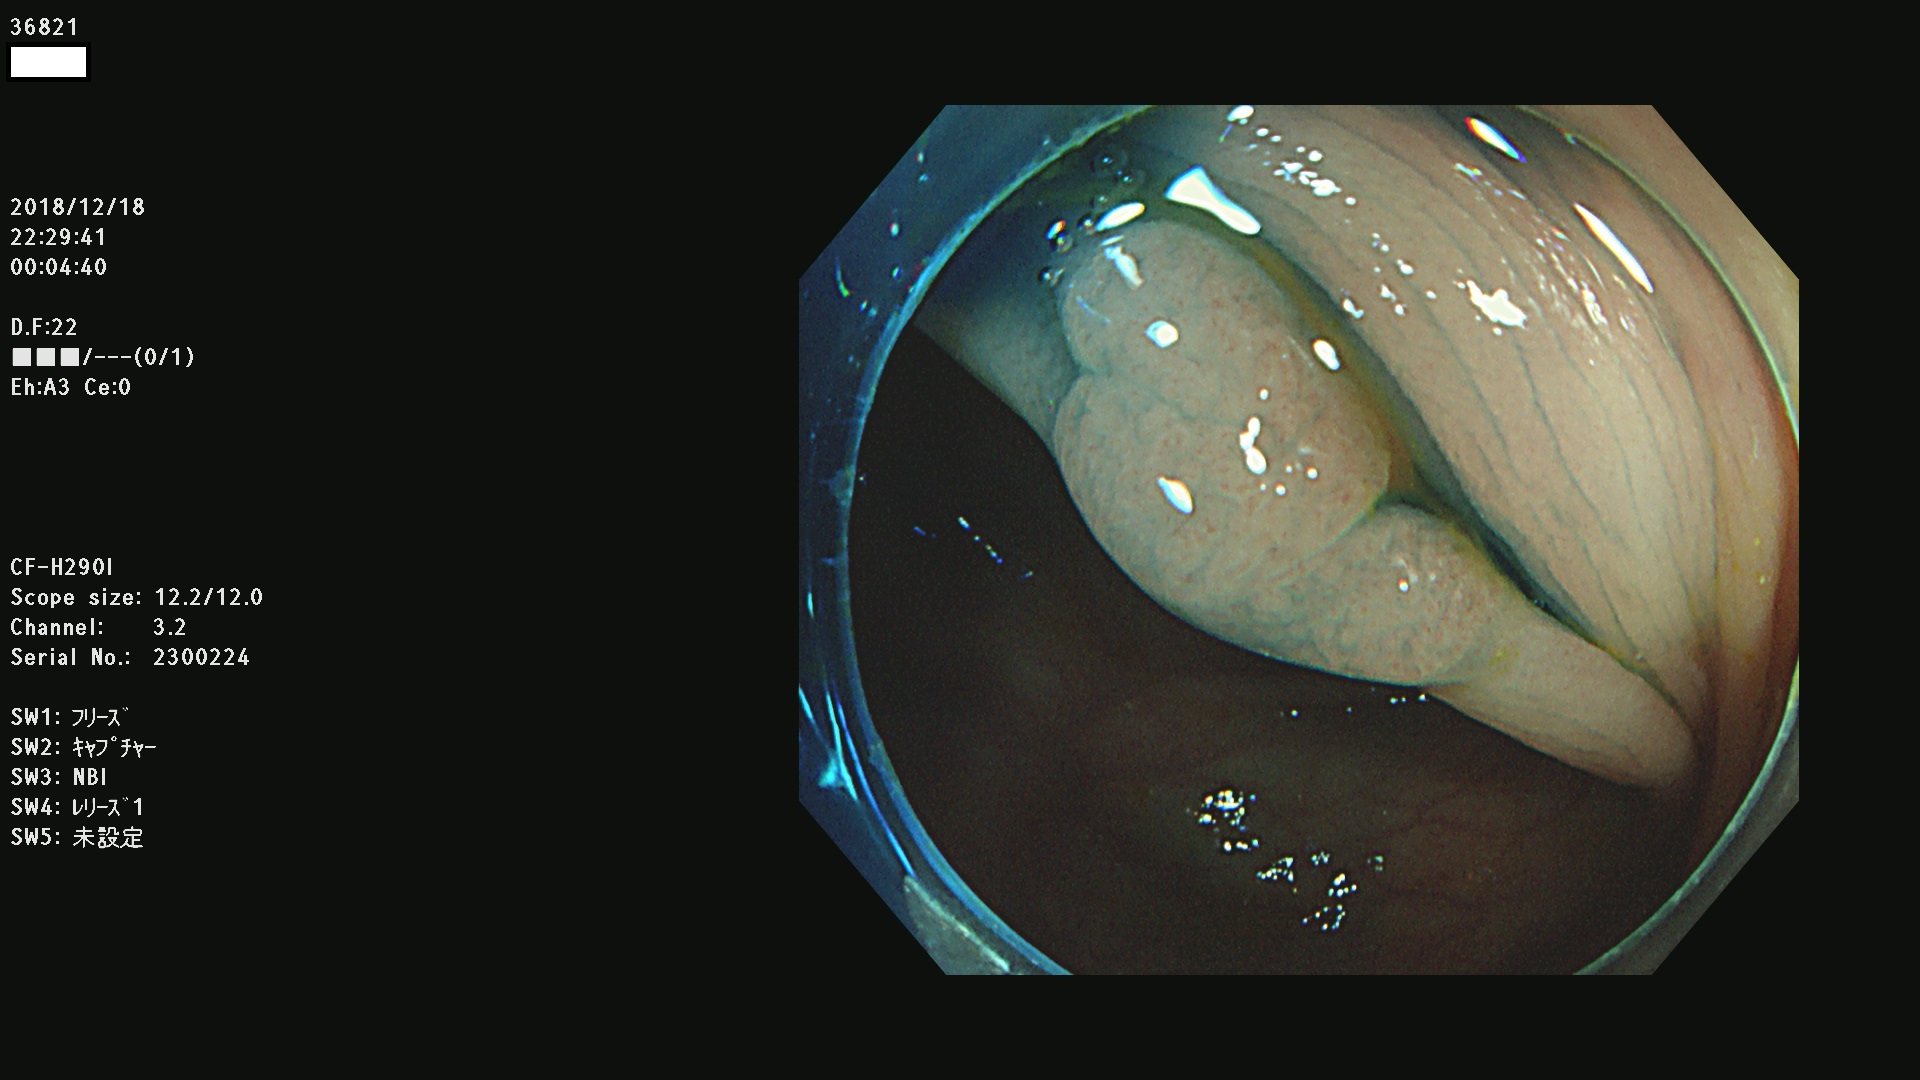

36804 36806 36807 36808 36809 36810 36811 36813 36815 36816 36817 36818 36820 36821 36822 36824 36825 36826 36828 36829 36830 36831 36832 36833 36834 36835 36837 36840 36841 36842 36845 36846 36848 36849 36851 36852 36853 36854 36855 36857 36859 36860 36861 36862(SSAPのみ) 36863 36864 36866 36868 36869 36870 36873 36875 36877 36878 36879 36881 36882 36883 36884 36885 36886 36887 36888 36889 36891 36892 36893 36894 36895 36896 36897 36898 36899

発見困難で危険性の高い平坦型病変(上記100名より抽出)